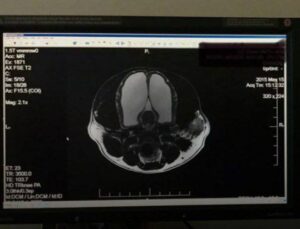

Хозяин узнал, что у его собаки почти отсутствует мозг — МРТ показало, что сохранилось лишь около 5%.

Несмотря на это, животное жило обычной жизнью и даже имело потомство. После первых припадков врачи смогли лишь рекомендовать поддерживающий уход.

Собака прожила ещё шесть лет, пока припадки не стали слишком частыми